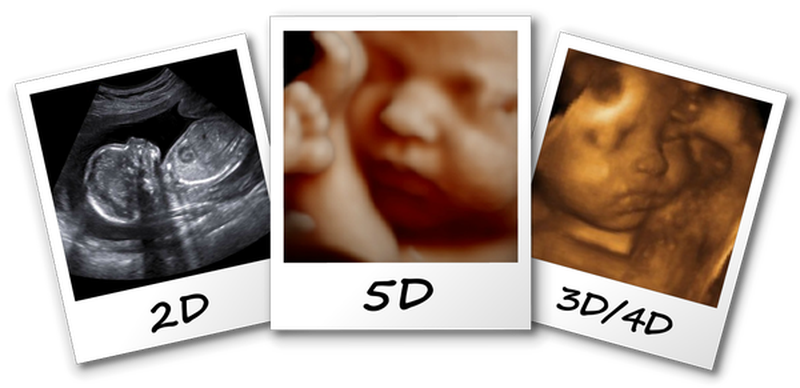

Những điều cần biết về kỹ thuật siêu âm 5D

Siêu âm 5D là một trong các kỹ thuật siêu âm hiện nay. Siêu âm 5D được đánh giá là tiên tiến, hiện đại hơn so với các kỹ thuật siêu âm truyền thống như siêu âm 2D, siêu âm 3D.... Cùng tìm hiểu kỹ hơn về kỹ thuật siêu âm 5D nhé!

Siêu âm 5D thực chất là kĩ thuật siêu âm cho phép các bác sĩ quan sát được hình ảnh động của các cơ quan và bộ phận bên trong cơ thể. Về bản chất siêu âm 5D chính là siêu âm 4D kết hợp thêm với các phần mềm chẩn đoán tự động hóa.

Siêu âm 5D được ứng dụng các công nghệ vô cùng tiên tiến và hiện đại, chính vì vậy nó sở hữu rất nhiều ưu điểm vượt trội hơn hẳn so với các phương pháp siêu âm truyền thống như siêu âm 2D, 3D, 4D. Siêu âm 5D sẽ giúp cha mẹ và bác sĩ có thể quan sát rõ nhất có đặc điểm về hình dáng cũng như các cử động của thai nhi.